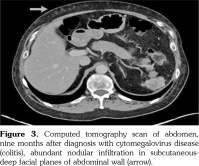

In clinical admission, his physical examination showed no evidence of systemic infection with a body temperature of 37.2°C. Laboratory findings at his first admission were summarized in Table 1. Computed tomography (CT) scan revealed a cavitary lesion of 6 mm in diameter located in the left upper lobe (which was also seen in his previous chest CT) besides a shrunken spleen as a recent finding (Figure 1).

Eight months afterwards, he was hospitalized with a body temperature of 38.3°C and fatigue. On this admission, laboratory examinations revealed high C-reactive protein (4.76 mg/dL) level while no bacterial growth was observed in blood cultures. PCR test detected CMV DNA at 2,400 copies/mL. CT scan of the abdomen showed new abundant nodular infiltration in the subcutaneous-deep facial planes of the abdominal wall (Figure 3). Abdominal subcutaneous fat tissue true-cut biopsy was performed and CMV DNA was detected in the quantitative PCR assay of tissue specimen. He was put on oral valganciclovir treatment while mycophenolate mofetil was permanently discontinued. Following antiviral therapy, azathioprine was started and peripheral blood PCR assay revealed CMV DNA of 57 copies/mL at one month of this treatment.